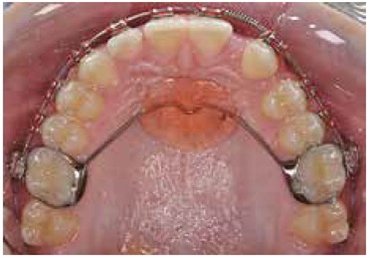

The Nance appliance has a band (like a ring) made of stainless steel that goes around the permanent first molars. A stainless steel wire is welded to these bands that arches the inner surface of the upper teeth. In the region behind the upper front teeth, an acrylic material is used to fabricate a circular structure called the acrylic button. The wire remains stable because of this acrylic material. Nance appliance works by restricting the movement of the first permanent molar. It is a fixed appliance whose hygiene needs to be maintained. In some cases, this appliance can also be used to correct the position of a rotated molar.